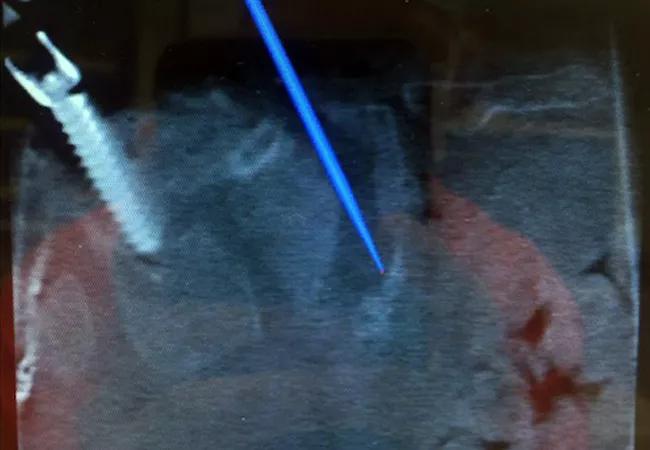

At Cleveland Clinic, MISS procedures are performed routinely, and intraoperative navigation is often used to assist in complex revision and deformity operations, as demonstrated by the two cases presented in images below. Case 1 illustrates a minimally invasive transforaminal interbody fusion with the use of intraoperative navigation to place cortical screws and a 3-D-printed interbody cage. Case 2 illustrates the use of intraoperative CT navigation to place iliac fixation in a patient with a Charcot lumbosacral arthropathy.

Case 2. Images from the case of a 21-year-old woman with a history of paraplegia who developed a lumbosacral Charcot arthropathy after a T4-ileum reconstruction. Preoperative imaging studies (top left) show the Charcot arthropathy. Intraoperative navigation was used (top right and bottom left) to identify the extent of the bone loss and aid in the placement of lumbopelvic fixation. Intraoperative imaging (bottom right) shows the placement of four iliac screws.